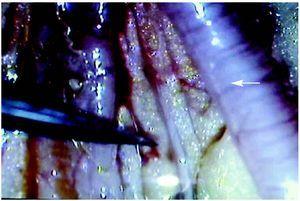

Figura 3. Localización del uréter en relación con el cuerno uterino. Señalizado con instrumental se muestra el uréter y con flecha, el cuerno uterino.